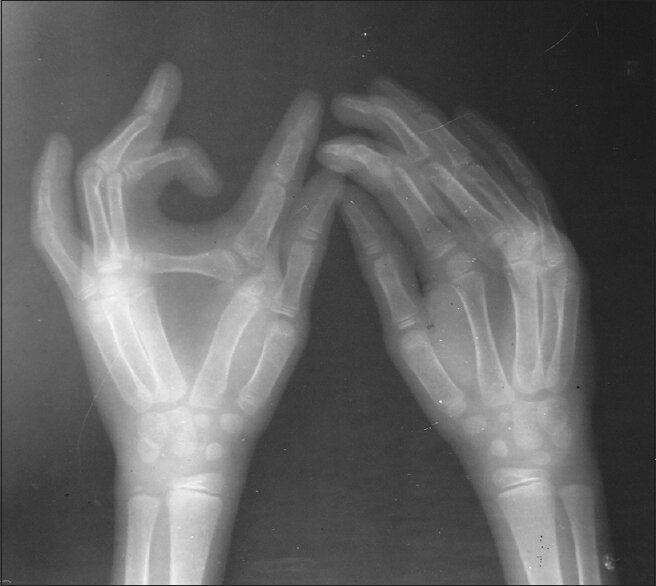

Эктродактилия - врождённое заболевание вызванное делецией, транслокацией и инверсией в 7-й хромосоме. Основной признак этого заболевания - клешнеобразные кисти руки или стопы. В среднем, заболевание встречается у 1 из 10 000 человек. Заболевание имеет больше косметологический дефект и люди, которые в итоге не проводят операцию по исправлению внешнего вида стопы\кисти, ведут вполне обычную жизнь. Но конечно, людям в современном обществе очень тяжело жить спокойной жизнью с такими дефектами, причём основная проблема носит именно психологический характер.